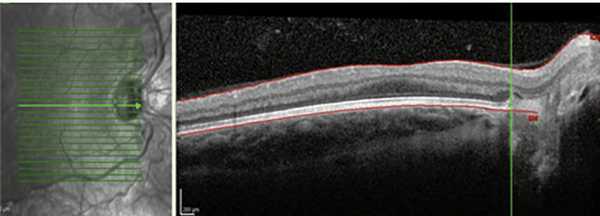

При анализе клинического состояния глаз у глубоко недоношенных пациентов выявлены некоторые особенности. На 10 (18,5%) из 54 глаз с благоприятными исходами РН, на которых в активной фазе РН локализовалась в I или II зоне, наблюдались смещение ретинальных сосудов и тракция сетчатки в носовую сторону. Данный факт свидетельствует о более ранней манифестации заболевания в назальном отделе сетчатки, что характерно для детей, рожденных на ранних сроках гестации (рис. 2) [4, 9].

Рис. 2. Смещение ретинальных сосудов и эктопия макулы в носовую сторону (данные ОКТ).

Результаты проведенной ОКТ показали, что у глубоко недоношенных детей с благоприятными исходами РН на 33 (61%) из 54 глаз отмечалось нарушение анатомического контура макулы. На 12 глазах с остаточными изменениями I—II степени сглаженность фовеолярного контура в совокупности с сохранностью эмбрионального строения макулы (слоев нейроэпителия в фовеа) свидетельствовала о нарушении дифференцировки макулы вследствие недоношенности, и лишь на трех глазах она сопровождалась снижением остроты зрения ниже 0,3. На 10 глазах со II степенью РН сглаженность фовеолярного контура сопровождалась наличием структурных изменений (кистовидный отек и тракционная деформация нейроэпителия), невидимых при офтальмоскопии, что и объясняло некорригируемое снижение остроты зрения. При III степени РН сформированный фовеолярный контур и сохранность слоев нейроэпителия в макуле выявлены только на двух глазах. В остальных случаях фовеолярный контур был сглажен или отсутствовал вследствие тракционной деформации макулы после перенесенной РН и коррелировал со сниженной остротой зрения (рис. 7).

Рис. 7. Сглаженный фовеолярный контур и тракционная деформация сетчатки на глазу с рубцовой РН III степени.